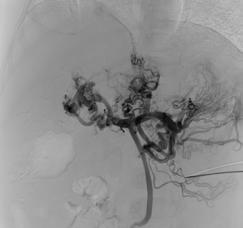

Pascual's care team included medical oncologist Claire Mulvey, MD, and radiologist Thomas Hope, MD, who worked closely together throughout the course of his treatment, which included Peptide Receptor Radionuclide Therapy (PRRT). PRRT is a molecular therapy often used to treat neuroendocrine tumors (NETs) using a radioactive substance that is attached to a peptide designed to bind to receptors on the surface of tumor cells.

“For Jonathan, although PRRT has not removed the majority of his tumors, stabilizing his disease has allowed him to do the things that he enjoys,” said Hope.

“I am amazed by the joy that Jonathan brings to life. He does not let his cancer define the road he will travel,” Hope added. “We often see our patients through the images we take, but there is no relationship between Jonathan’s smile and what one can only call extensive metastases on his imaging.”

Peptide Receptor Radionuclide Therapy

Peptide Receptor Radionuclide Therapy (PRRT) is a targeted cancer treatment that uses a radioactive substance (radionuclide), attached to a peptide (DOTATATE), to deliver radiation directly to neuroendocrine tumors (NETs).

How PRRT works:

The peptide is designed to bind to somatostatin receptors found on the surface of certain cancer cells. The radionuclide, Lutetium-177, a radioactive isotope that emits radiation, when attached to the peptide, delivers radiation directly to a patient’s tumor cells to treat the tumor.

PRRT is commonly used to treat patients with advanced or metastatic neuroendocrine tumors to control tumor growth, reduce symptoms, and may improve quality of life for patients. There are no available FDA approved therapies to treat paraganglioma, but PRRT can be an effective therapy in a subset of these patients.